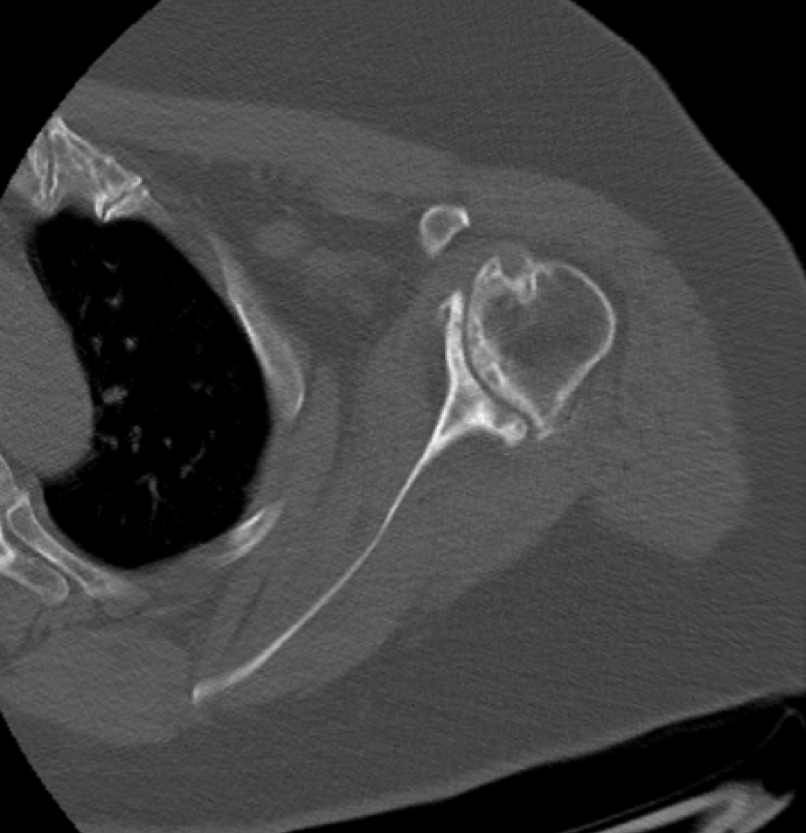

Pre-op

- 67-year-old female

- Severe pain

- Cuff tear athropathy

- Severe glenoid destruction

Surgical Plan

- Glenoid restoration with Bio RSA

- with appr. 10 mm thickness (allograft)

- Pre-op planning using the mediCAD 3D Shoulder Module